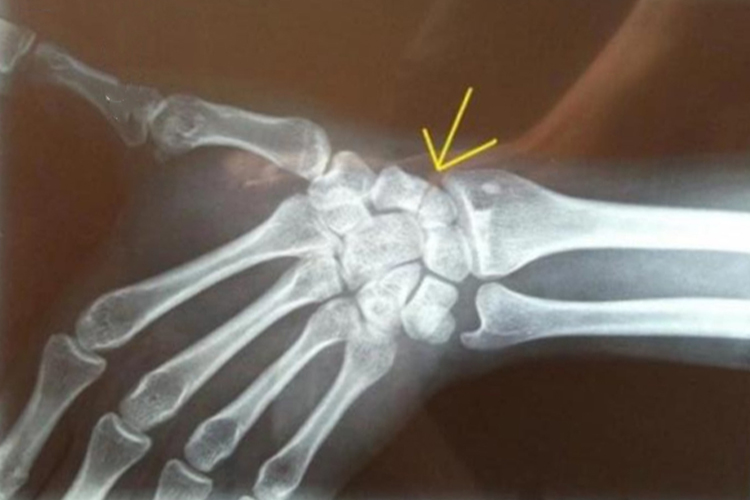

夜班接诊1例罕见的急性腕舟骨半脱位

图片尺寸5792x4344